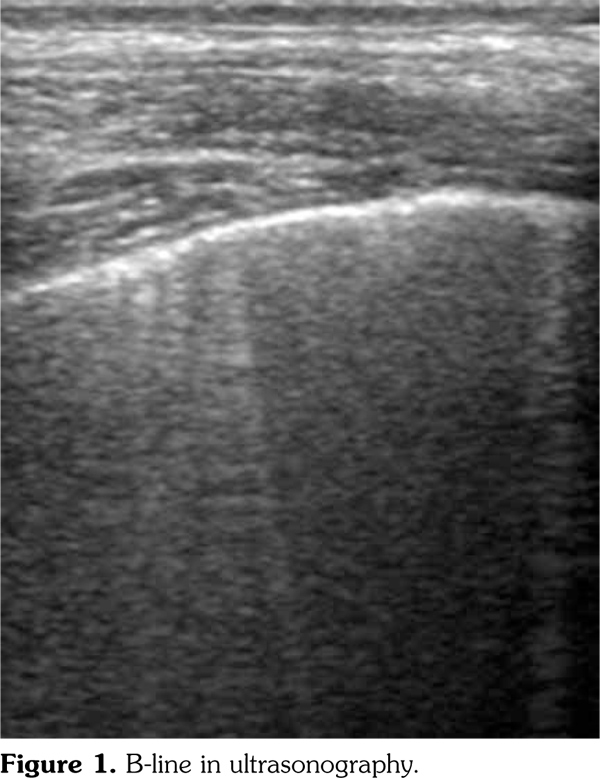

Ultrasonography has also been begun to be used in the evaluation of interstitial fibrosis particularly in patients with connective tissue diseases. USG is a cheap, safe, non-ionizing method which can be applied easily on bedside. B-lines may be seen particularly in interstitial pulmonary disease and are identified as “lung comets” in USG. These are images that take origin from thickening of interlobular septa and may be used as a biomarker to show fibrosis.(9)

Using USG, patient’s anterior chest wall was evaluated in the supine position while the posterior chest wall was evaluated in the sitting position with a linear probe (L38E/5-10 MHz, SonoSite, Inc.). Systolic pulmonary artery pressure (sPAP) over tricuspid regurgitation was calculated with the modified Bernoulli equation formula with a sector probe (P17/1-5 MHz, Sonosite Inc.). We obtained B-lines which consisted of a total of 14 bilaterally involved lung intercostal spaces (LIS). For the anterior chest, the authors considered the second LIS along the parasternal lines, the fourth LIS along the midclavicular, the anterior axillary, and the midaxillary lines. For the posterior chest, the eighth LIS along the paravertebral, the subscapular, and the posterior axillary lines were selected. The reason for choosing these regions was to detect more ultrasonographic B-lines and also because these are the regions that can be evaluated by a USG. The number of B-lines was recorded for every LIS (Figure 1). When the number of B-lines were ≥3 in a region or >5 in adjacent spaces, they were accepted as positive. If there was a fully white appearance in a region, it was accepted to be 10 B-lines.(12) The B-lines total sum of all LIS was recorded. According to the semiquantitative method, we recorded as follows: 0= normal (B-lines <5); 1= mild (B-lines 6-15); 2= moderate (B-lines 16-30); 3= prominent (B-lines >30).(9)